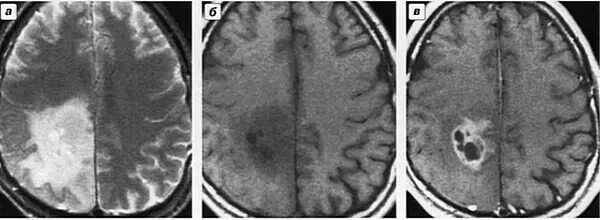

Рисунок. Опухоль головного мозга.

а) и б) – Т1 и Т2 режимы без контрастирования;

в) исследование с контрастом, при котором четко видна сама опухоль, остальное отек.